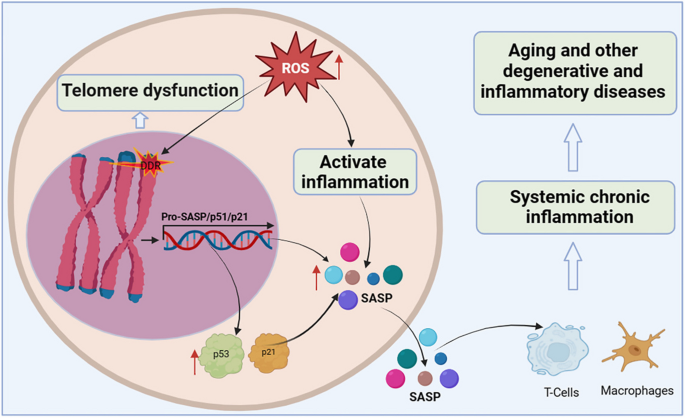

Organismal cellular telomere reserves are limited, and the loss of telomere function is closely associated with age-related adaptive decline [ 99 , 100 , 101 ] (Fig. 4 ). Excellent telomere and telomerase structures are essential for ensuring the normal physiological function of mothers and offspring, and their integrity has a certain genetic intergenerational effect [ 102 , 103 ]. Mice with knockout of TERT that are crossbred in successive generations, the telomeres of the offspring gradually shorten, finally developing telomere dysfunction in the third generation [ 104 ]. Additionally, low telomerase levels and continued tissue turnover lead to decades of progressive telomere attrition in the progenitor cells of highly proliferative tissues, including the haematopoietic system, gastrointestinal tract, and skin [ 10 , 11 ]. Excessive telomere attrition ultimately triggers DDR such as cell cycle arrest [ 105 ], apoptosis [ 106 , 107 ], differentiation disorders [ 108 ] and senescence [ 109 ]. Notably, as the aging process progresses, hypoproliferative tissues, including the heart, brain, and liver, may suffer from the effects of reactive oxygen species (ROS), which further induce telomere sequence damage, telomere attrition, and uncapping [ 86 , 110 ]. Thus, the aforementioned telomere properties make them a focal point in the biology of aging.

Telomere dysfunction activates DDR to drive cellular senescence. ROS induce telomere sequence damage, leading to telomere shortening and decapitation, triggering DDR, inducing the overexpression of cell cycle inhibition markers p53 and p21, and accelerating cell senescence. Senescent cells secrete SASP, which alter extracellular matrix composition, recruit and enhance T cells and macrophages, which can spread the aging phenotype to surrounding cells, thus promoting systemic chronic inflammation and inflammation-related diseases

Shortening of telomeres to a critical length leads to replicative cellular senescence [ 86 , 111 , 112 , 113 ]. Chromosomal telomeres gradually shorten as DNA replicates. When telomeres reach a critical length, they cannot bind enough telomere-covering proteins and are perceived as exposed DNA ends [ 114 ]. One or a few very short telomeres are sufficient to trigger the DNA damage response and induce overexpression of the cell cycle inhibitory markers p53 and p21, thereby forcibly inhibiting cell proliferation [ 115 ]. Accumulated senescent cells secrete a complex set of pro-inflammatory cytokines, termed the senescence-associated secretory phenotype (SASP), including interleukins, interleukin chemokines, proteases, and growth factors. The SASP alters the composition of the extracellular matrix and propagates the senescent phenotype to surrounding cells, leading to systemic chronic inflammation [ 116 ]. Interestingly, persistent telomere cohesion protected aged cells from premature senescence [ 117 ]. Therefore, telomere dysfunction-associated DNA damage response signalling events are key determinants of cell fate and organismal aging.

In summary, telomeres and telomerase play important roles in the core mechanisms that drive aging and many major human diseases. However, many knowledge gaps remain, such as the elucidation of the mechanisms regulating telomerase expression and activity, the non-canonical function of TERT, and the interactions between telomere dysfunction, inflammation, fibrosis, and degenerative disease. Therefore, there is an urgent need to develop telomerase activators for the treatment of aging and age-related diseases to prevent and treat fatal diseases caused by telomere shortening by rescuing telomeres and telomerase damage.